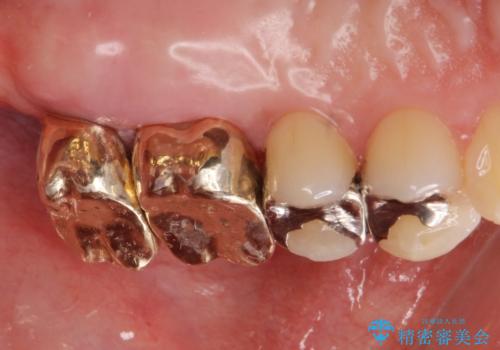

- 銀歯をやりかえたいが他院で抜歯と言われセカンドオピニオンで来院。適合の悪い被せ物が入っており、まずは古い材料、虫歯をとり保存可能か確かめる必要があり、拡大鏡下で全て取り除いたら歯質が歯茎の中まで虫歯がありました。このまま無理やり型取りをして被せ物を作っても不適合な被せ物が入る可能性が高いため歯茎を切り取る手術(ディスタルウェッジ)を行いました。そして再根管治療を行いゴールドの被せ物で治療を行いました。